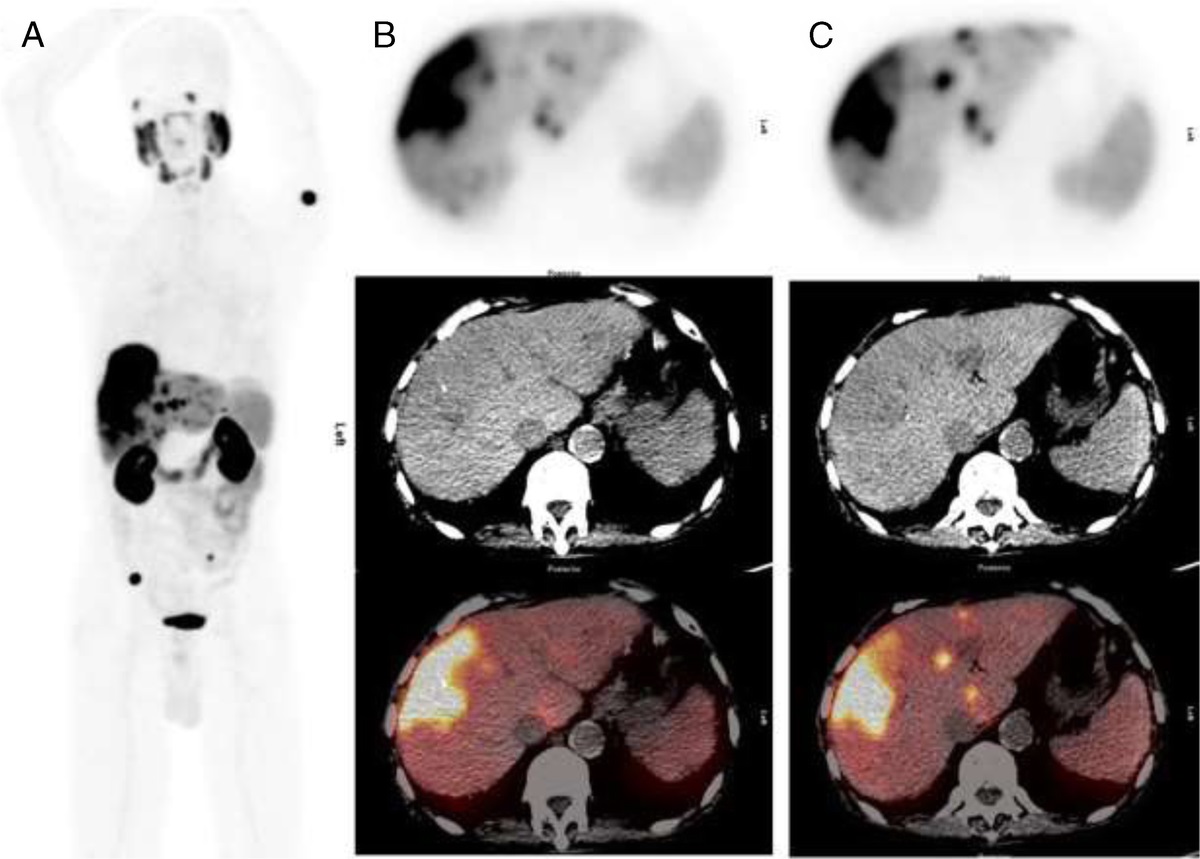

Novel Radiopharmaceuticals and Future of Theranostics in Genitourinary Cancers in European Urology authors.elsevier.com/c/1jyul14kplyz… Thanks Dr Martina Sollini Ospedale San Raffaele and co-authors: Jeremie Calais Louise Emmett prof. Stefano Fanti Ken Herrmann Thomas Hope Brian Shuch, MD